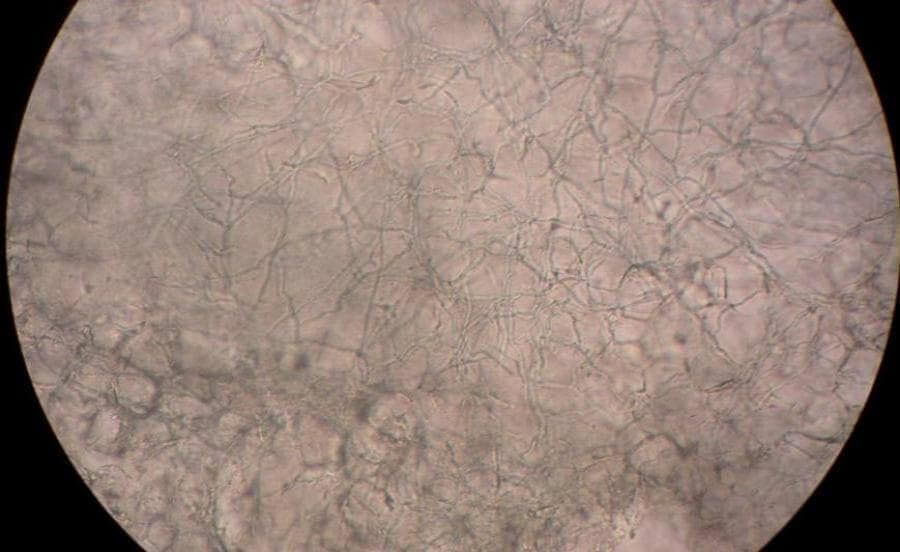

Schimmels zijn overal. Ze zitten bij iedereen op het lichaam. Dit is meestal niet erg. Op uw huid zit een vetlaagje dat u beschermt en zorgt dat u geen klachten krijgt.

Soms werkt die bescherming minder goed. Bijvoorbeeld als het vetlaagje van uw huid eraf gaat. De schimmel komt dan uw huid binnen en kan daar groeien. U krijgt dan plekken tussen uw tenen of op uw voeten.

De schimmel zit in schilfers van de huid. De schilfers laten los van de huid en komen op bijvoorbeeld de vloeren van zwembaden, doucheruimtes en sportruimtes. Als u deze schilfers op uw huid krijgt, kunt u voetschimmel krijgen.

– “Ide” reactie op een huidinfectie. Rode jeukende blaasjes aan de zijkanten van de vingers en handpalmen als een uiting van een overgevoeligheidreactie op een infectie elders in de huid. De bekendste voorbeeld is een schimmelinfectie aan de tenen of voet (= zwemmerseczeem). Ook een ernstige schimmelinfectie aan de voeten op zich kan hierbij eruitzien als blaasjeseczeem.